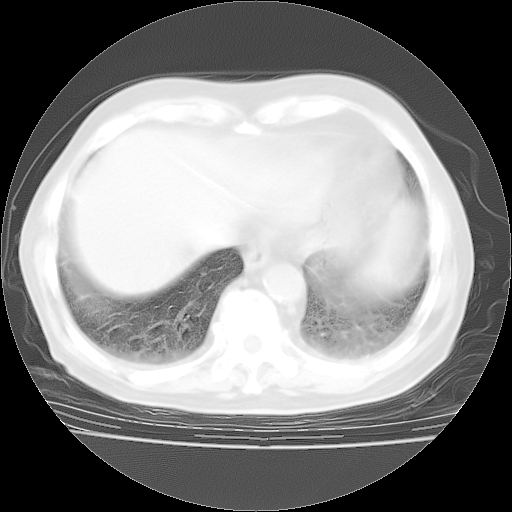

轻微咳嗽,无痰,(体温正常时)R20次/分,P75次/分,双肺底、腋下可闻及少量捻发音。下肢轻度浮肿。

ECG:右心室增大

心脏超声检查:无右心室增大。